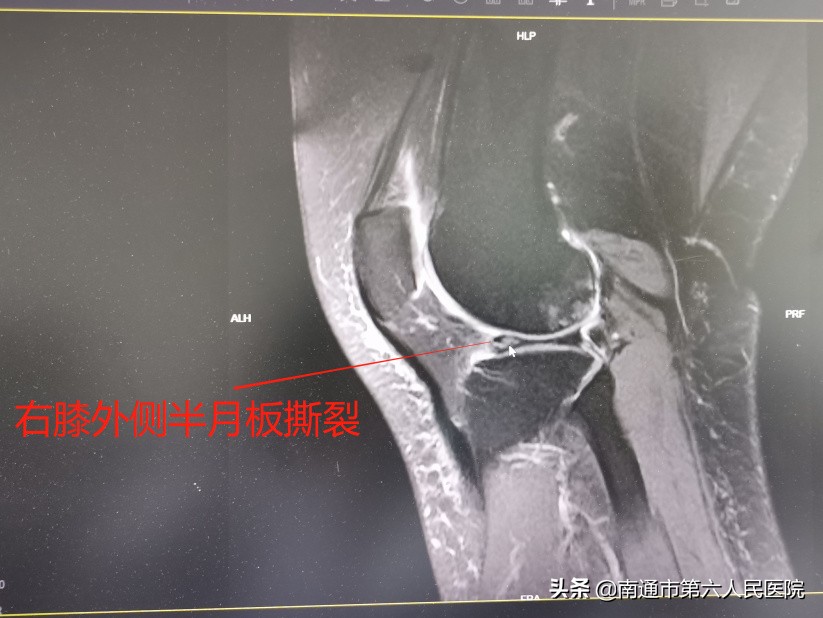

近日,秦女士因为受伤的右膝疼痛加重,来到南通市第六人民医院(上海大学附属南通医院)关节外科就诊,她说:“这几天疼痛加重了,特别是上下楼梯和下蹲的时候,疼痛更明显,有时候还会突然无法伸直,像是被卡住了,这才意识到问题的严重性,赶紧来医院就诊。”果不其然,核磁共振检查提示,秦女士右膝外侧半月板撕裂,而且属于三度损伤。

半月板严重撕裂,两个小孔精细修复

在排除了手术禁忌症后,邓院长治疗团队为秦女士及时安排了关节镜手术。术中,通过关节镜探查,证实了术前的诊断,秦女士半月板撕裂严重,而且关节软骨也受波及,出现了斑驳的损伤。关节外科手术团队通过精细修整成形后,半月板又被牢固的固定到了关节囊上,“重新上岗”继续发挥缓冲压力稳定关节的作用。